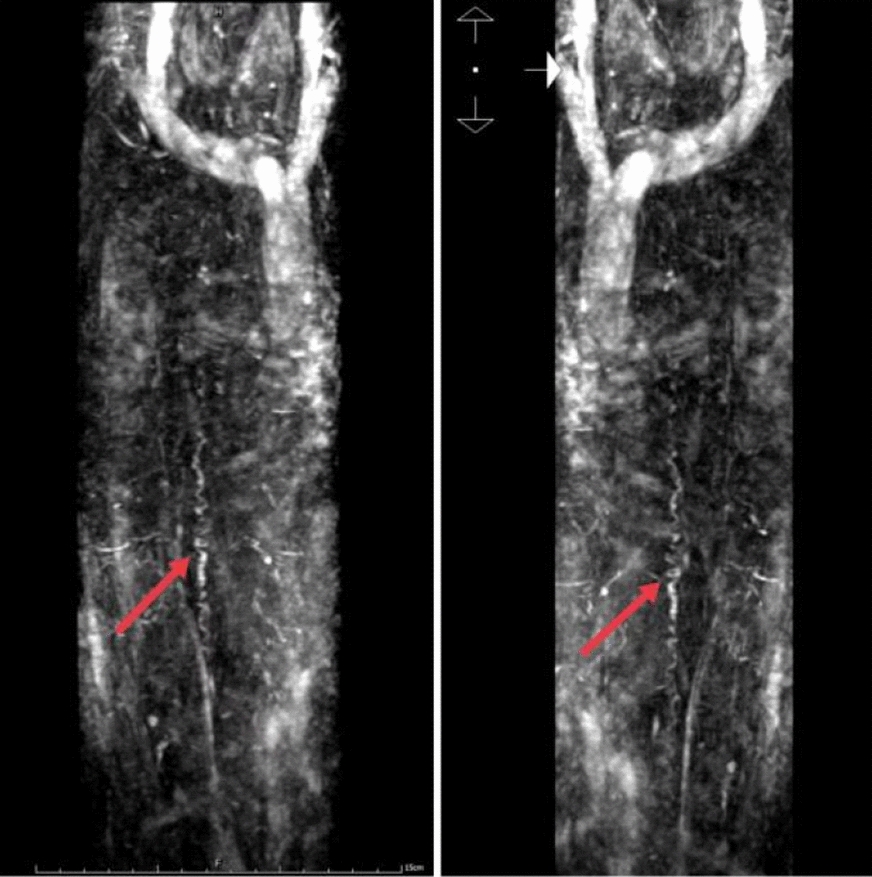

Case presentation: A 76-year-old Chinese male patient presented with numbness and weakness of the lower limbs that rapidly progressed to complete paralysis within 4 days. Patient was diagnosed with spinal dural arteriovenous fistula after magnetic resonance imaging and spinal vascular angiography, undergoing bilateral internal iliac artery embolization 2 weeks later, and started rehabilitation 40 days later but only received minimal improvement 1 year thereafter.